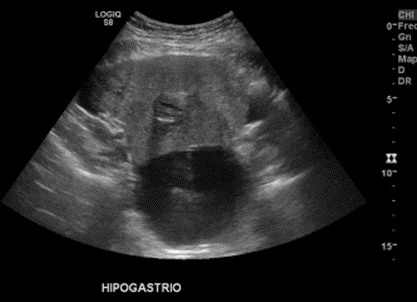

Se observa además en hipogastrio masa solidoquistica, principalmente sólida, isoecogénica con señal al Doppler, de bordes definidos, sugerente de omental cake

Destaca en este estudio dos quistes complejos en región anexial derecha con componente sólido nodular excéntrico, con leve vascularización periférica de 4,5 x 4,1 cm y 8,6 x 7,8 cm asociado a masa parauterina derecha en íntimo contacto con estos quistes, ecogénica, heterogénea, de contornos irregulares, con leve vascularización periférica, de aproximadamente 10,8x9,5 cm.

Quistes complejos en región anexial derecha (2) asociado a masa parauterina derecha y ascitis, hallazgos que podrían estar en relación a neoplasia ovárica. Es indispensable complementar estudio con TAC de abdomen y pelvis para mejor caracterización